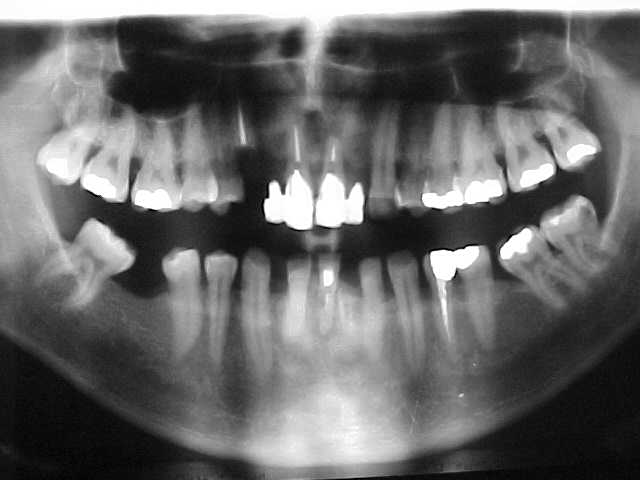

Vista oclusal (imagem refletida no espelho) anterior ao ínicio do tratamento

Modelos de estudo antes do tratamento